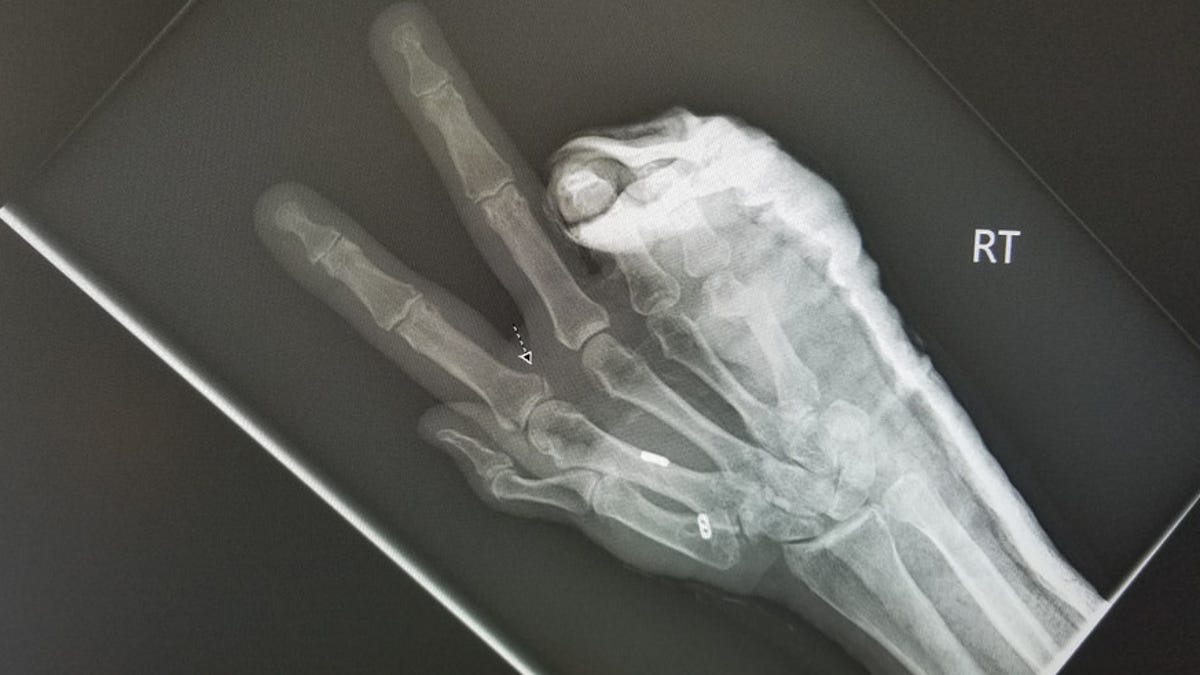

Two surgeries later, Brogan ended up with a broken metacarpal held together with two metal pins in her right hand, along with a cracked knuckle joint, road rash and a hematoma down her entire right leg. Her left hand was so badly swollen, doctors had to cut off her rings.

This 31-year-old woman was in a scooter accident in Santa Monica, California, in October and broke three bones in her ankle that required surgery, a metal plate and screws.